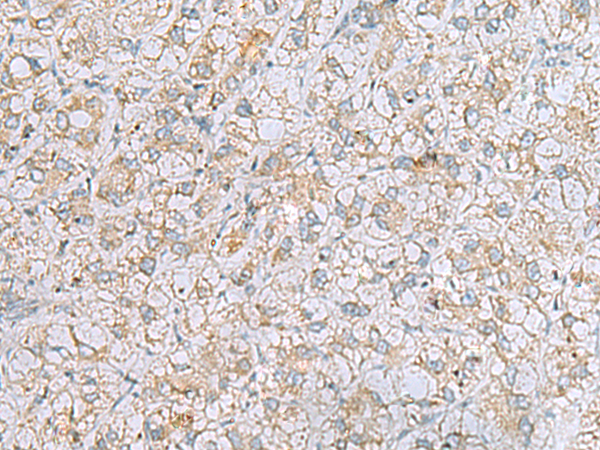

分类: 科研抗体货号: P12772别名: NAG14; NGL-2应用: IHC反应种属: Human, Mouse, Rat